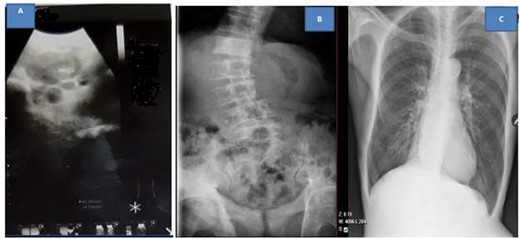

Abdominal pelvic ultrasound showed right moderate hydronephrosis with multiple pelvic masses that were separate from heterogeneous prostatomegaly (Fig. 1A). Kidney, ureter and bladder (KUB) X-ray revealed multiple osteoblastic lesions on the iliac wings and lumbar vertebrae (Fig. 1B); however, chest X-ray was normal (Fig. 1C). Abdominopelvis computed tomography scan was ordered but due to financial constraints, the patient was unable to afford, thus the staging was done by combination of the clinical presentation of the patient; (T3) as the prostate capsule was hard with an extra-capsular extension; (N3) due to the presence of supraclavicular lymph node involvement and (M1a) for the presence of osteoblastic lesions on the bone from the X-ray (Fig. 1C).

Ultrasound showing pelvic masses (A), kidney, ureter and urinary bladder X-ray showing osteoblastic lesions (B), and normal chest X-ray (C)